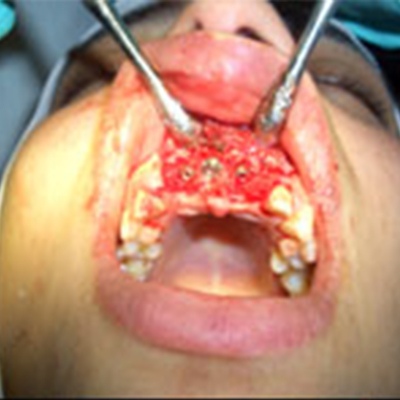

Bone Grafting

Over a period of time, the jawbone associates with missing teeth atrophies or is reabsorbed. This often leaves a condition in which there is poor quality of bone suitable for the placement of dental implants. However, we now have the ability to add or grow bone where needed. In most cases, synthetic or demineralized bone is placed in a socket after a tooth is extracted or at the time of implant placement. These materials speed up the integration process and allow new bone to grow around the implant. Patients who have been missing teeth for many years may require a more extensive surgery in which bone is taken from their chin or hip and grafted to their jaw. After approximately six months of healing, the jawbone is then ready for the placement of implants. Bone grafting technology not only gives us the opportunity to place implants of proper length and width, it also gives us a chance to restore functionality and esthetic appearance.